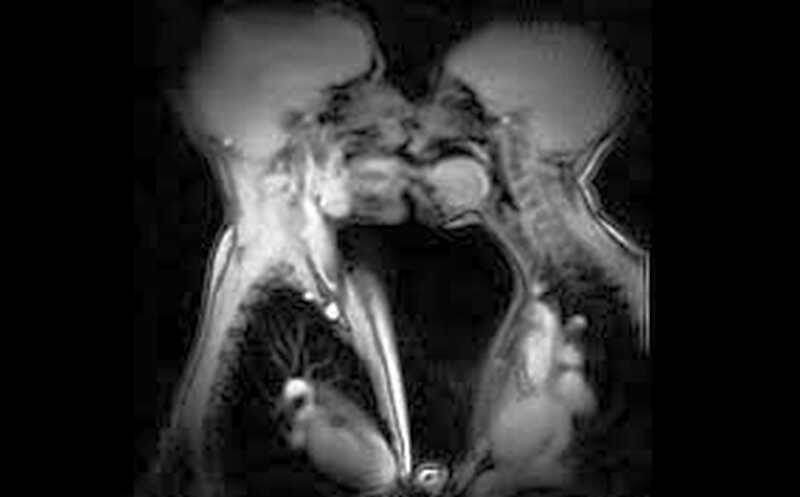

Размер влагалища:

• Глубина в возбуждённом состоянии: 9–13 см (от входа до шейки матки) 4.

• Влагалище эластично: может расширяться до 2–3 раз при родах или глубоком проникновении.